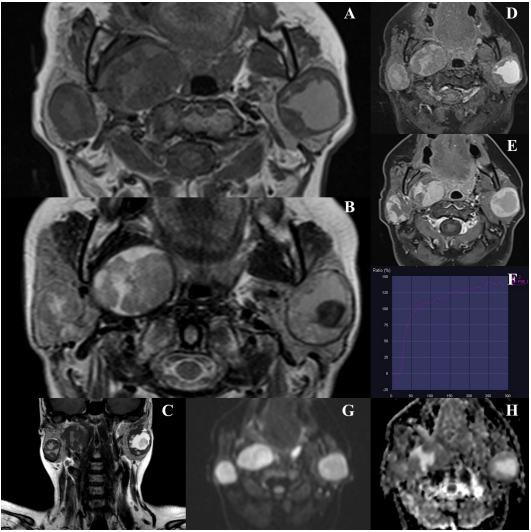

应用标准T1和T2加权序列以及弥散加权成像(DWI)和动态对比增强T1加权脂肪饱和序列进行磁共振成像(MRI)。检查证实左侧腮腺浅叶内(3.6 × 3.2 × 3.7cm)和对侧腮腺浅叶下部(2.9 × 2.6 × 3cm)存在肿瘤。右侧腮腺深叶的第二个病变(4.8 × 3.6 × 4cm)延伸到咽旁间隙(图2)。三个病灶边缘均光滑、清晰。表现为异质结构,具有中央囊性区域,部分具有较高的蛋白质含量和出血迹象。基于动态对比增强序列获得的时间-强度曲线显示对比剂的持续摄取,提示腺瘤。肿瘤没有表现出扩散的迹象,表观扩散系数(ADC)值约为1.48 × 10−3 mm2/s(图3)。

图2. 双侧多灶性腮腺基底细胞腺瘤的MRI表现

图3. 右侧腮腺全切除术后的轴向T2加权MRI图像显示了术后部位的标准视图,左侧腮腺浅叶有一个残余病变